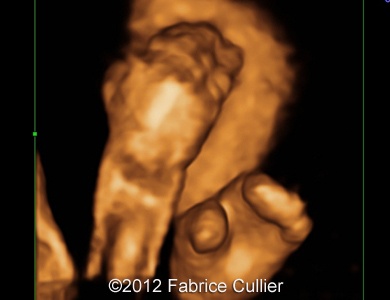

Images 8, 9: Abnormal foot with syndactyly of the four fingers, big toes positioned at right angles

6A(1)

6B(1)

Image 10, 11: 3D evaluation of the toes.

7A

7C